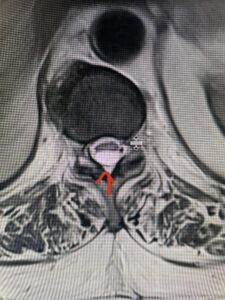

Fig 2a Sagittal and axial T2 weighted cervical MRIs demonstrating large C4 5 herniated disc with spinal cord compression red arrows

This 47-year-old male who four months prior was lifting weights developed sharp pain in his neck. After that he developed progressive numbness in his arms, neck pain and headache. He said that the right arm was worse than the left. On examination the patient had long tract weakness on the right side which included his triceps, finger extensors, hip flexors, and dorsiflexors. The patient did not have hyperreflexia. MRI (Fig. 2) demonstrated a massive, extruded disc herniation with severe cord compression. The patient because of progressive myelopathy and spinal cord compression was indicated for anterior cervical discectomy and fusion at C4-5 (Fig. 3). Patient had significant improvement of weakness and numbness post operatively.

Fig: 2b Axial T2-weighted cervical MRI demonstrating spinal cord compression from C4-5 herniated disc (red arrow)